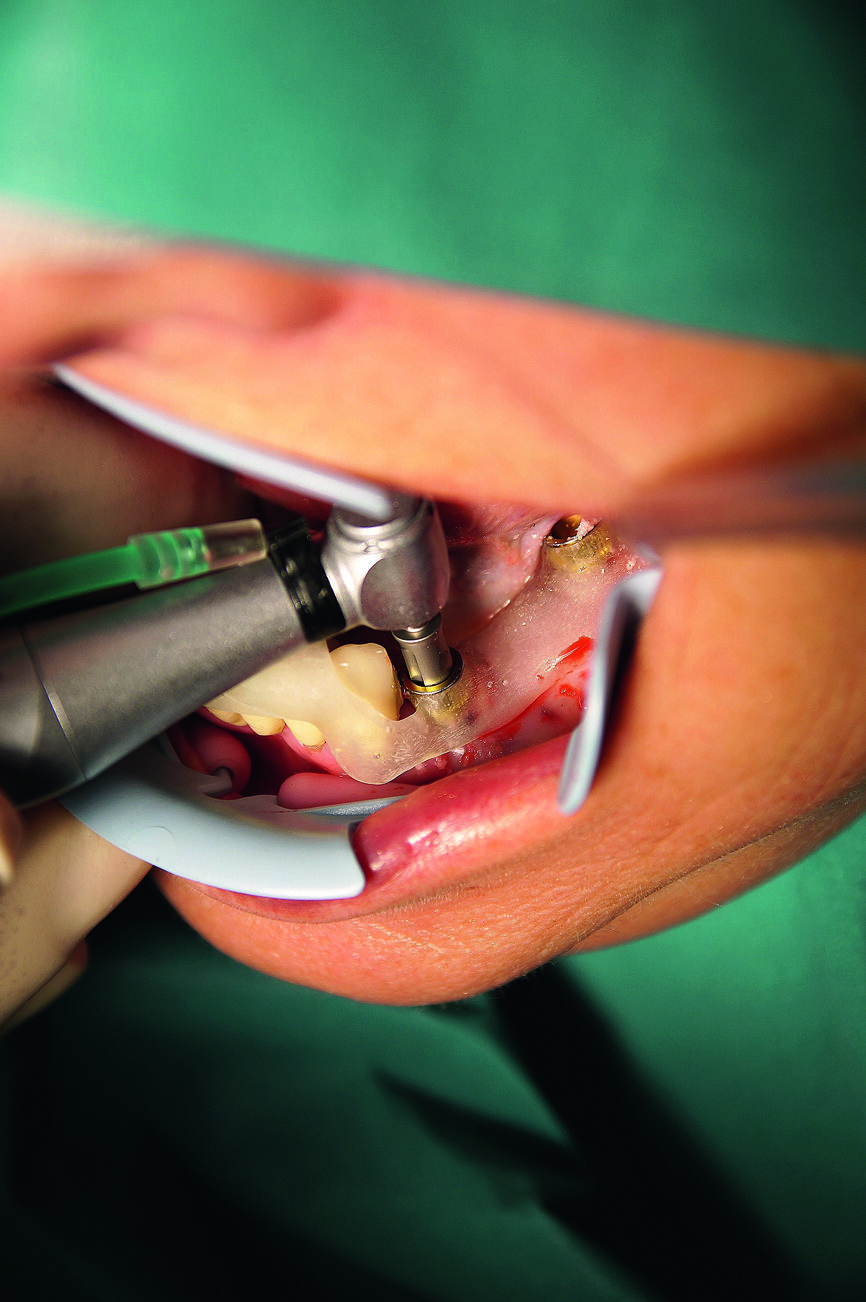

Dans la mandibule, la muqueuse a été perforée avec un emporte-pièce rotatif au niveau des sites dentaires 36, 34, 32, 42, 44 et 46 (Fig. 14). Après le retrait du gabarit, les endroits de la gencive marques a l’aide de l’emporte-pièce ont été incises davantage et les bouchons de gencive découpée éliminés, afin d’obtenir une mandibule perforée et préparée (Fig. 15). Ensuite, le gabarit de forage a été remis en place. Des forêts à cannelures droites (foret-guide de 6 mm ; forets de mise en forme de 9, 11 et 13 mm) ont été utilisés pour préparer les ostéotomies implantaires au niveau des sites dentaires 36, 34, 32, 42, 44 et 46, conformément aux instructions du fabricant (Fig. 16).

Le traitement chirurgical a été réalisé sous anesthésie locale par Ultracain D-S forte 1 : 100 000. Un antibiotique (cefuroxime 500 mg) a été administré une heure avant la chirurgie puis deux fois par jour pendant six jours. Le patient s’est rincé la bouche avec une solution à base de gluconate de chlorhexidine (0,2 %) pendant une minute avant l’intervention. Après une anesthésie par infiltration dans le maxillaire et la mandibule, et une anesthésie tronculaire bilatérale dans la mandibule et le palais supérieur, le guide chirurgical a été soigneusement mis en place et stabilisé dans la mandibule.

Le guide chirurgical a été correctement positionné dans la cavité buccale par rapport à l’arcade antagoniste. Une attention particulière a été apportée à la mise en place du guide chirurgical (Fig. 7). Après son positionnement correct et sa stabilisation, la chirurgie implantaire sans lambeau a été réalisée conformément au protocole de forage établi pour le type d’implant utilise (Fig. 8). Deux implants CAMLOG de 4,3 mm de diamètre et 13,0 mm de longueur ont été insères selon une technique totalement guidée au niveau des sites dentaires 34 et 44, et des implants de 4,3 mm de diamètre et de 11,0 mm de longueur au niveau des sites dentaires 36 et 46.

Fig. 8 : Forage guidé à travers le manchon de forage selon le protocole chirurgical.